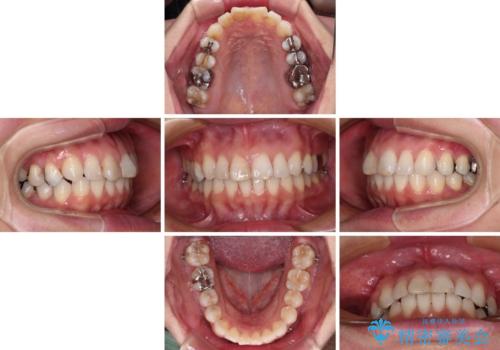

- 前歯のデコボコを治したいとのことで来院された患者様です。

上下顎ともに歯列全体の後方移動とIPR(歯と歯の間を削る)によってデコボコが解消するように設計し、インビザラインにより治療を行うこととしました。

しっかりと装着時間を守ってくださったのですが、途中妊娠にともなう悪阻や出産といったイベントがあり、予定よりも治療期間が長くなりました。